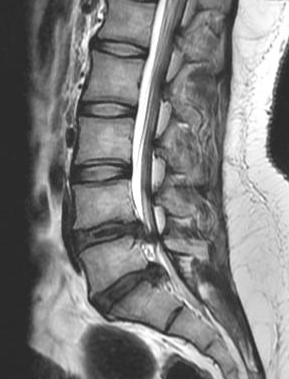

She came to see me in this condition in our spine clinic just 48 hours before the important exam. After a clinical examination it was obvious we needed a MRI of the lumbar spine as it looked like a disc prolapse causing severe nerve root compression. An MRI of the lumbosacral spine was done immediately and she had disc prolapse at two levels causing severe nerve root compression and that was the reason for her symptoms. She was explained about the problem and given the option of bed rest and medications or a root block injection. But she wasn’t willing to give up the examination for which she had prepared putting in a lot of hard work. She insisted on a more definitive treatment for her leg pain. She was advised to undergo an endoscopic discectomy and the pros and cons were explained. She consented for the procedure and it a two level interlaminar endoscopic discectomy using Destandu endoscope was done at L4/5 and L5/S1 levels the same evening. She recovered well and was able to walk without leg pain and was able to sit comfortably for over half an hour by next morning. She was discharged from the hospital the next evening after surgery.